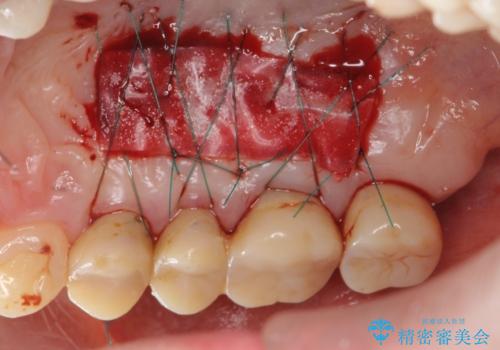

また、機能後のインプラント周囲の清掃性を高めるため遊離歯肉移植術を行っています。

インプラント周囲に強固な歯ぐきを移植することで、歯ブラシがしやすくなりインプラント周囲炎対策となります。